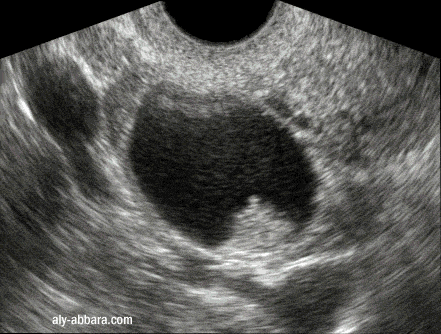

Kyste de l'ovaire droit, fonctionnel avec hémorragie

intra-kystique sous forme d'une fausse végétation endophytique